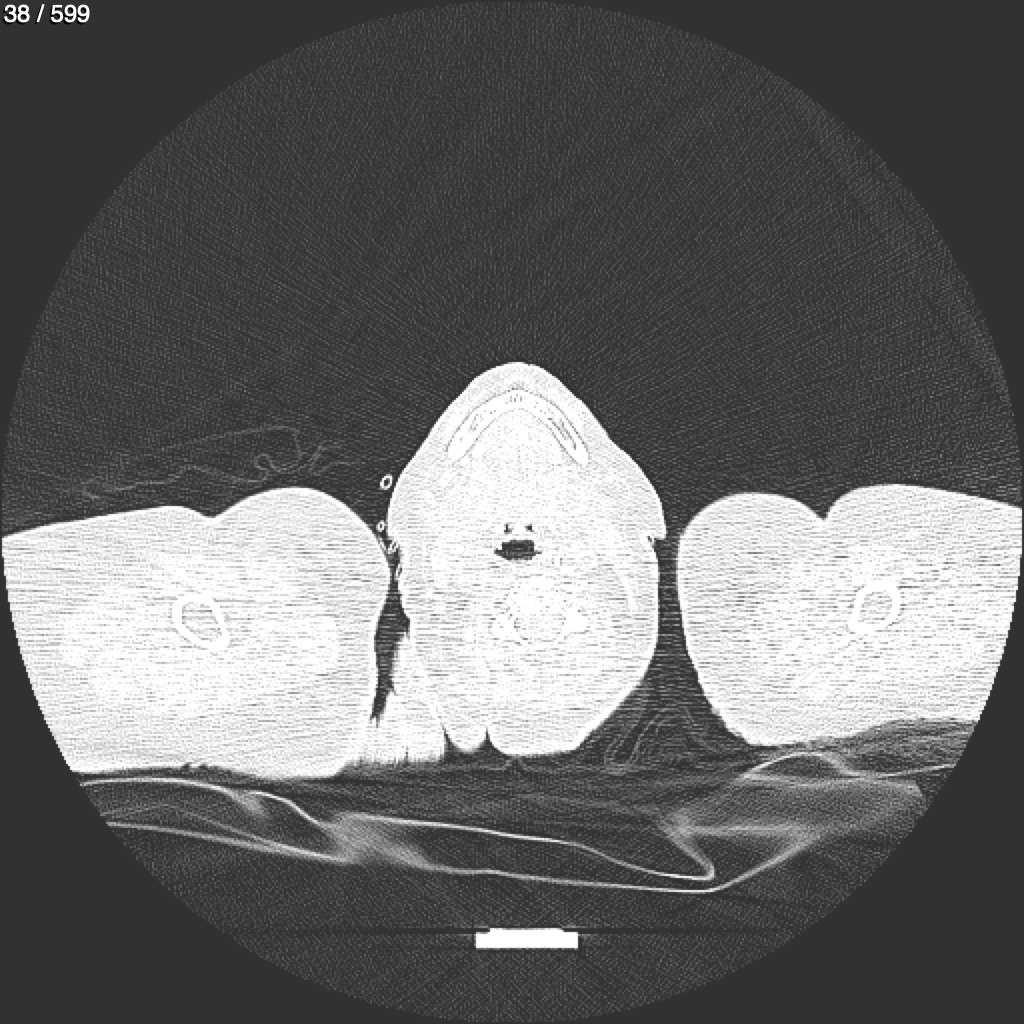

Home G​l​o​r​i​a​ ​G​l​a​d​y​s​ ​B​e​a​s​l​e​y​ ​-​ ​T​ó​r​a​x​ ​T​o​r​a​x​_​S​i​m​p​l​e​ ​(​A​d​u​l​t​o​)